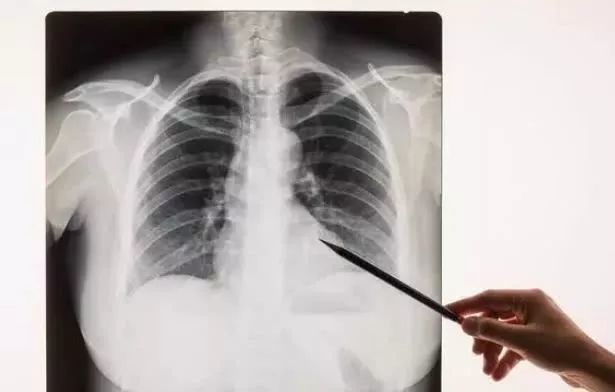

90的受检者体检都会被胸片这个伪影吓到是肺结节

正常的胸片图